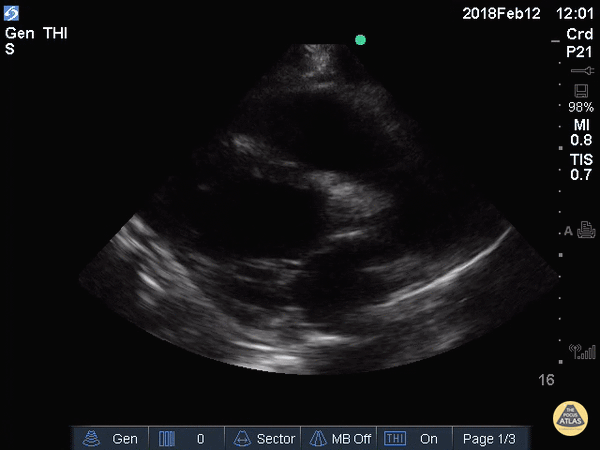

Subcostal View

• ANATOMIC LANDMARK: just below xiphoid

• Heart is ANTERIOR structure and mostly MIDLINE

• Probe flat, directed toward head, marker to the right

• Downward pressure

• SONOGRAPHIC LANDMARK: HEART

• Identify: LV, RV, LA, RA, MV, TV

• Pericardium +/- Pericardial fluid